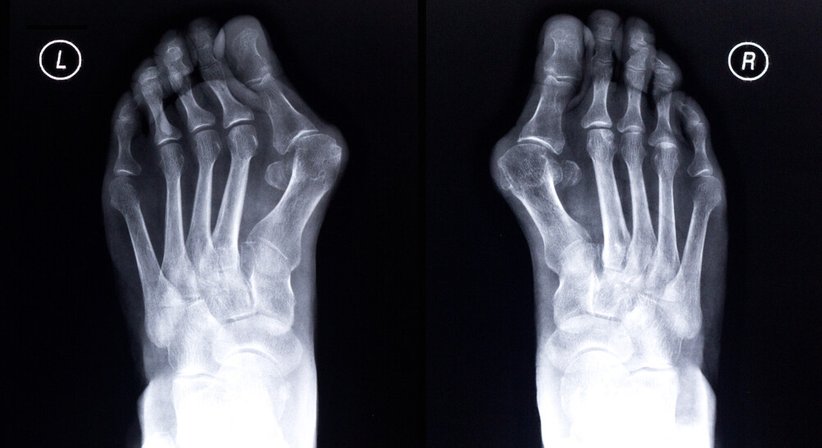

Hallux valgus

Als Hallux valgus wird eine Fehlstellung im Großzehengrundgelenk bezeichnet, die in erster Linie Frauen betrifft. Zu den Ursachen der Deformität zählen eine genetische Veranlagung und das Tragen von zugespitzten, engen Schuhen.

Ein Hallux valgus stellt oftmals nur ein rein kosmetisches Problem dar. Schreitet die Fehlstellung der Großzehe jedoch voran, kann es zu starken lokalen Schmerzen mit Schwielen und Hühneraugen kommen. Lassen sich die Beschwerden durch konservative Maßnahmen (u.a spezielle orthopädische Einlagen oder breitere Schuhe) nicht beheben, ist eine Operation indiziert.